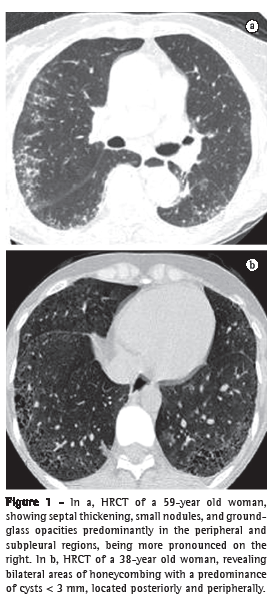

b) HRCT, which was performed with a GE device (model HiSpeed LX/i; General Electric Medical Systems, Milwaukee, WI, USA) as follows: 1-mm slices, at 1.5-s intervals and increased by 10 mm; image reconstruction with a 512 × 512 pixel matrix, using a high-resolution algorithm; a window width of 1,000 HU; and a mean window level of −700 HU. The HRCT findings were interpreted by two independent radiologists with experience in interstitial lung disease. The scans were analyzed for the following: small nodules; ground-glass opacities; septal thickening; honeycombing; and traction bronchiectasis. As shown in Figure 1, the patients were divided into two groups by the presence or absence of honeycombing (17 and 18 patients, respectively).

There was no disagreement between the radiologists about the presence or absence of interstitial pneumonia or about the diagnostic HRCT findings. The major HRCT abnormalities were small nodules (rounded opacities< 1 cm), septal thickening, and ground-glass opacities, detected in 30, 29, and 26 cases, respectively. Honeycombing was found in 17 cases and was interspersed with areas of patchy ground-glass opacity in 13 of those cases. Traction bronchiectasis with associated areas of honeycombing was observed in 13 cases.

Honeycombing is seen primarily at the lung bases, predominantly in the peripheral and posterior regions of the lungs, and is frequently accompanied by traction bronchiectasis. In the present study, the HRCT scans revealed honeycombing in 48.6% of the cases, which is similar to the 56.0% reported in another study conducted in Brazil.(7)